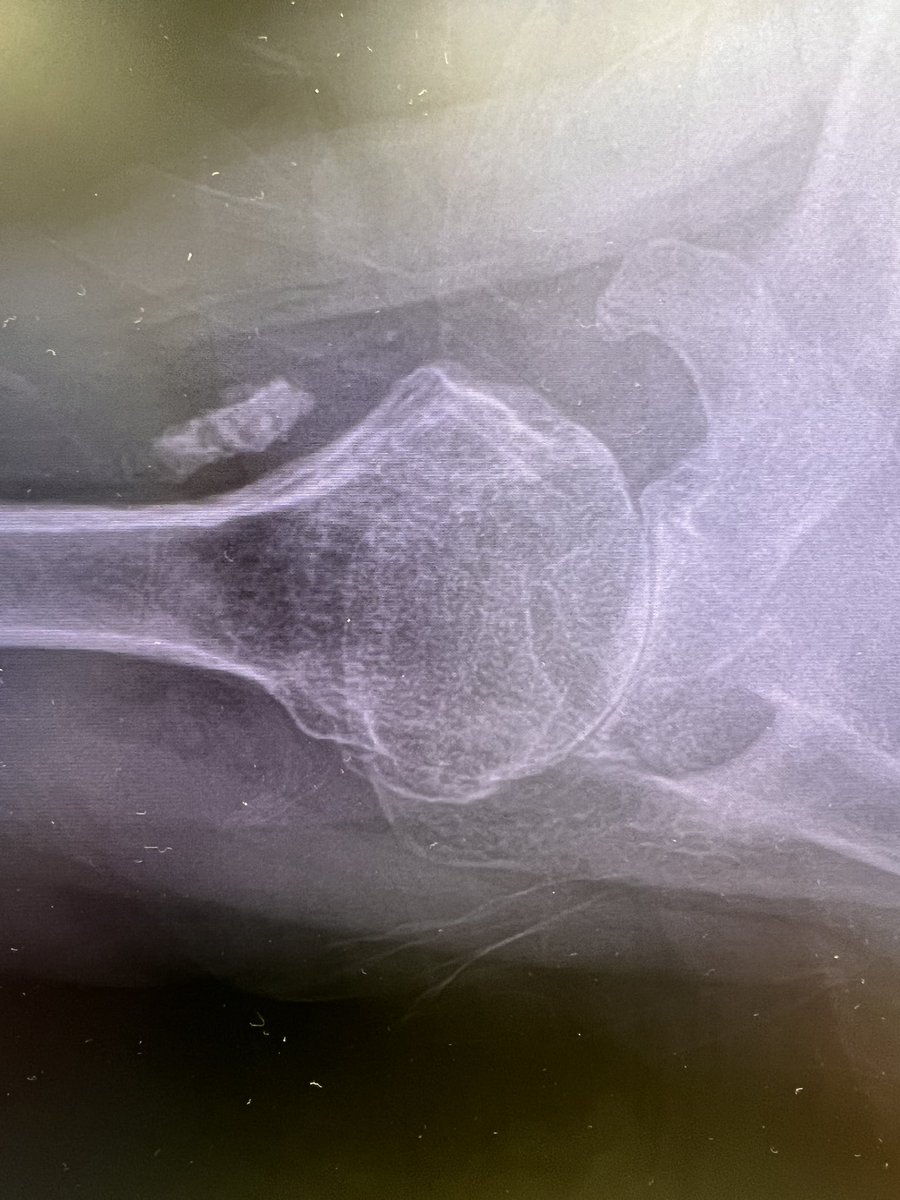

Incredibly excited to officially start my practice as a Shoulder and Elbow Surgeon at @DMC_Heals! Looking forward to seeing patients in Detroit, Dearborn, and Warren.

Orthopaedic Shoulder & Elbow Surgeon at Detroit Medical Center (Detroit, Dearborn, Sterling Heights). Team Physician for Detroit City FC. Opinions are my own.